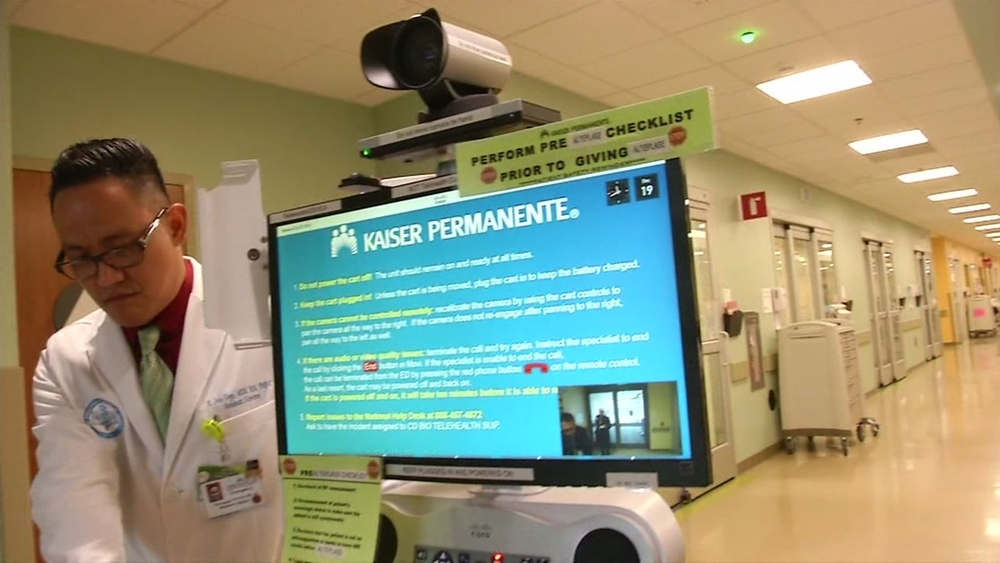

RELATED: Kaiser study shows new program cuts stroke treatment time in half